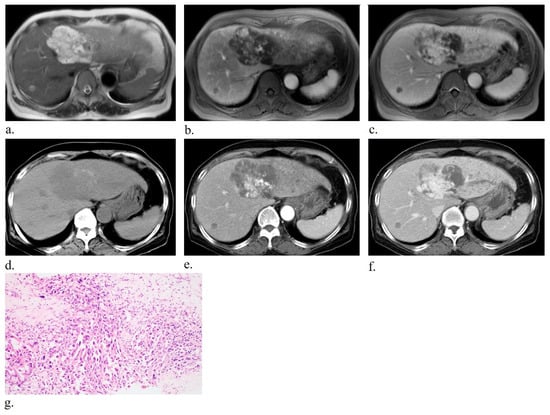

Primary Hepatic Angiosarcoma: Distinct Imaging Phenotypes Mirroring Histopathologic Growth Patterns in a Retrospective Human Study

Background/Objectives: To date, no studies have examined radiologic findings by histologic patterns of primary hepatic angiosarcoma; this study clarified radiologic findings of primary hepatic angiosarcoma according to distinct histologic patterns. Methods: From January 2010 to October 2024, 17 individuals (mean age, 69 years ± 11; 11 men) with pathologically confirmed primary hepatic angiosarcoma underwent computed tomography (CT) with or without magnetic resonance imaging (MRI). Histologic patterns were classified as mass-forming, subdivided into vasoformative and non-vasoformative (epithelioid and spindled) patterns, or non-mass-forming, subdivided into sinusoidal and peliotic patterns. Two radiologists independently reviewed CT and MRI images, classifying lesions as non-mass-forming or mass-forming. Hypervascular portions and targetoid patterns were also assessed. Associations between histologic patterns and radiologic findings were evaluated using Fisher’s exact test. Results: Mass-forming tumors were observed in 13 individuals (76.5%), and non-mass-forming tumors in 4 individuals (23.5%). Significant correlation (p < 0.05) was found between radiologic classification (non-mass-forming or mass-forming) and corresponding pathologic patterns. Pathologic subdivision into vasoformative and non-vasoformative patterns did not correlate with hypervascular portions on imaging. Conclusions: Pathological classification into mass-forming and non-mass-forming patterns corresponds closely to radiologic classification of mass-forming and non-mass-forming lesions, indicative of strong pathologic features in imaging. Full article

Show Figures

Figure 1